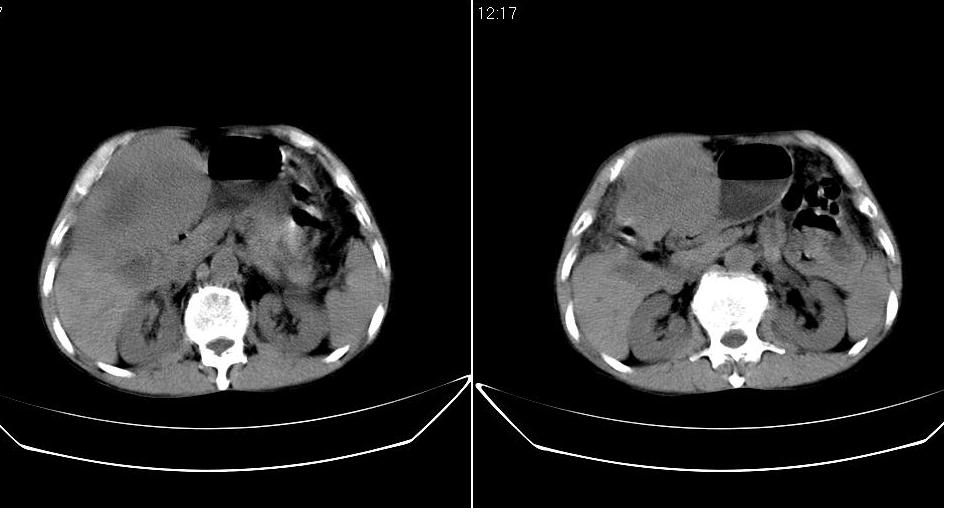

标题: CT20033:上腹部CT平扫

男 66岁,腹疼,b超提示考虑肝癌。

考虑巨块型型肝癌坏死、出血。建议增强。

考虑巨块型肝癌可能性大;建议行进一步检查。

考虑肝左叶巨块型肝癌可能性大;建议行增强ct扫描。